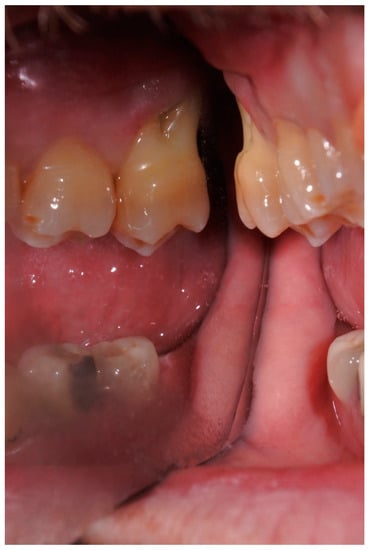

2.1. Case Presentation